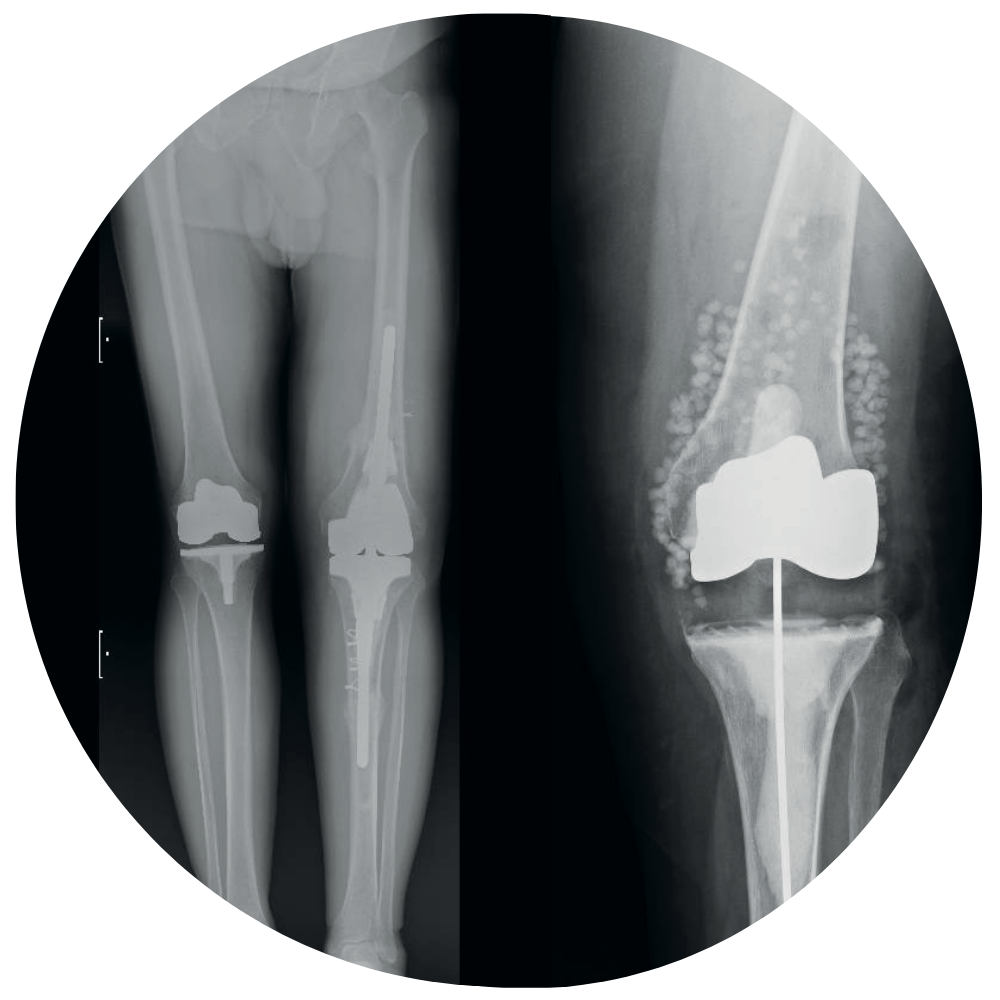

REVISIÓN DE ARTROPLASTIA DE RODILLA

Es un honor invitarlos al Curso Internacional: “Revisión de Artroplastia de Rodilla, Principios Básicos dentro de la Complejidad”, que se realizará los días 21 y 22 de noviembre de 2025 en Santiago de Chile.

El aumento exponencial de pacientes que requieren cirugías de revisión genera una importante presión económica y asistencial en los sistemas de salud, tanto públicos como privados, por lo que su adecuado manejo resulta fundamental para lograr resultados favorables.

Este curso estará enfocado en comprender las causas de fracaso en la artroplastia de rodilla, su diagnóstico, tratamiento y la prevención de complicaciones. Contaremos con la participación de destacados especialistas nacionales e internacionales, quienes compartirán su experiencia y conocimientos.